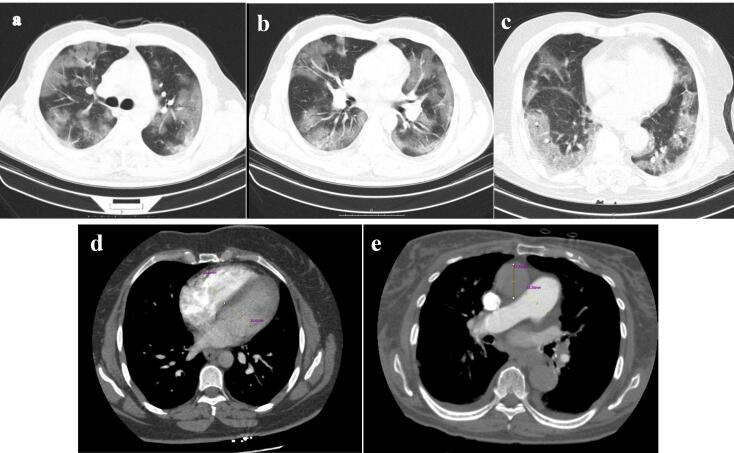

Introduction: It has been demonstrated that an increase in the diameter of the right ventricle or pulmonary artery in COVID-19 patients could be associated with the severity of lung involvement and may lead to unfavorable outcomes, particularly in the presence of pulmonary vascular diseases. This study investigated the relationship between these right heart strain features, the extent of lung involvement, and their prognostic values in patients without vascular comorbidities.

Methods: This study selected 154 consecutive patients with positive chest computed tomography (CT) findings and no evidence of concurrent pulmonary disease. Clinical characteristics and adverse outcomes in in-hospital settings were collected retrospectively. Diameters of cardiac ventricles and arteries, along with lung opacification scores, were obtained using CT pulmonary angiography (CTPA) findings, and the association of these variables was evaluated.

Results: An increase in pulmonary artery (PA) to ascending aorta (AO) diameter ratio and lung parenchymal damage were significantly and positively correlated (P=0.017), but increased right ventricle (RV) to left ventricle (LV) diameter ratio showed no association with the extent of chest opacification (P=0.098). Evaluating the prognostic ability of both ratios using logistic regression and receiver operating characteristic (ROC) analysis proved no significant class separation in regards to predicting adverse outcomes (PA/AO: OR:1.081, P Value:0.638, RV/LV: OR:1.098, P Value:0.344).

Conclusion: In COVID-19 patients without vascular comorbidities, a higher PA/AO diameter ratio was significantly associated with increased lung involvement severity on CT imaging but not with adverse in-hospital outcomes. Conversely, an increased RV/LV ratio on CTPA did not correlate significantly with adverse outcomes or the severity of parenchymal lung damage.